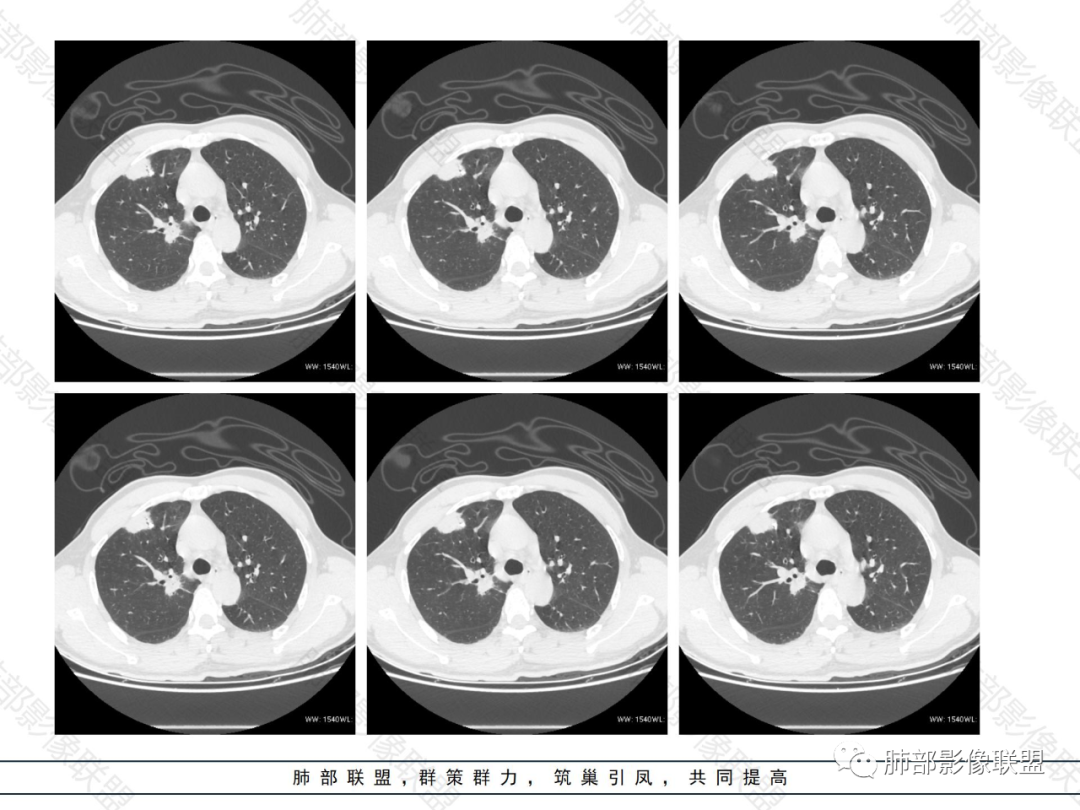

胸膜下多发实变病灶

外围胸膜下、支气管血管束分布

实变,密度较均匀

病灶的边缘平直、膨隆都有

内部支气管稍扩张,直达远端,或受压变形、移位

均匀强化

内部血管走形自然,稍纤细

支气管通畅、稍扩张、移位——不支持支气管来源

提示间质来源、周围肺实质来源

疾病普:淋巴瘤、血管炎性病变、隐球菌

占位效应与收缩性均匀,内部支气管稍扩张,或推移,淋巴瘤要考虑